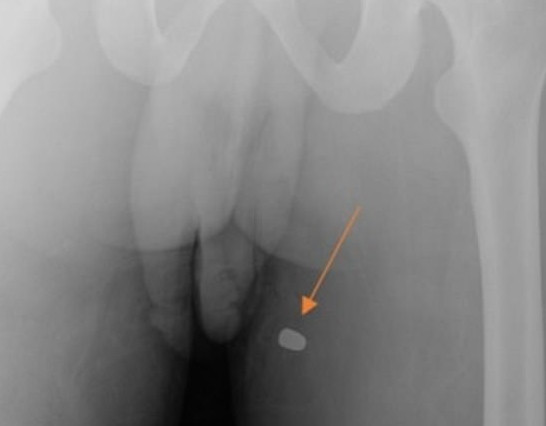

▲男子陰莖與大腿旁出現子彈傷。(圖/翻攝自Urology case reports)

紐約一間醫院的泌尿科日前接到一起臨床首例「陰莖中彈」的病例,會發現的原因是因該名病患生殖器官在勃起時偏左,醫師檢查時發現,在尖端處有一個洞孔,接著在進行X光檢測時發現,男子的大腿有一個傷口,看似是遭到子彈射擊的痕跡。

根據英國《每日郵報》報導,這名28歲的病患疑似為幫派分子,遭到槍擊後立刻被送往醫院,接著因為生殖器官出現角度不對稱、也不尋常的勃起,轉手泌尿科檢查後,醫師發現男子陰莖的尖端處有異常出血的情況,甚至有一個洞孔,疑似是被子彈直接通過,接著醫療團隊在男子的大腿上發現了一個傷口,照射X光後,推測應該是子彈最後擦到的傷口。

這項病例被發布的醫療期刊上,為臨床病例中首件「生殖器官」遭到子彈射擊的病例。醫療團隊表示,陰莖的海綿體在勃起時負責儲存血液,然而其中因為海綿體左側受到傷害,因此異常偏左勃起。醫師表示,要傷到陰莖的尖端,基本上機率相當低,這起案例的背後牽扯幫派的問題。